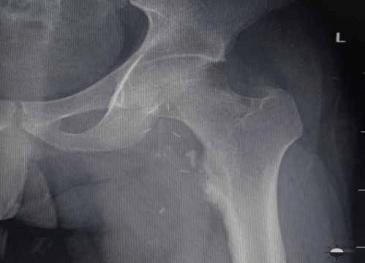

এখানে আমরা প্রক্সিমাল ফেমোরাল অস্টিওকন্ড্রোমার কারণে বাম নিতম্ব এবং উরুতে ব্যথা সহ একজন 28 বছর বয়সী পুরুষ উপস্থিত প্রতিবেদন করি। রেডিওগ্রাফ দেখায় ফুলকপির মতো ভর বাম প্রক্সিমাল ফিমার থেকে উদ্ভূত। বাম উরুর 3D CT স্ক্যান বিভাজনের কাছাকাছি ফেমোরাল জাহাজের সংকোচন পূর্ববর্তী স্থানচ্যুতি দেখায়। এই রোগীকে অস্ত্রোপচারের এন-ব্লক রিসেকশনের মাধ্যমে চিকিত্সা করা হয়েছিল এবং হিস্টোপ্যাথলজি অস্টিওকন্ড্রোমার ডায়াগনস্টিক ছিল।

অস্টিওকন্ড্রোমা বাম ফিমারের সাবট্রোচ্যান্টেরিক অঞ্চলের অ্যান্টেরো-মিডিয়াল দিকের উৎপত্তি যেখানে একটি বৃহৎ কার্টিলাজিনাস ক্যাপ সহ কম ট্রোক্যান্টারকে বিচ্ছিন্ন করে বিভাজনের কাছাকাছি ফেমোরাল জাহাজের সংকোচন পূর্ববর্তী স্থানচ্যুতি ঘটায়।

এক্স-রে করার আগে

প্রিওপ এক্স-রে